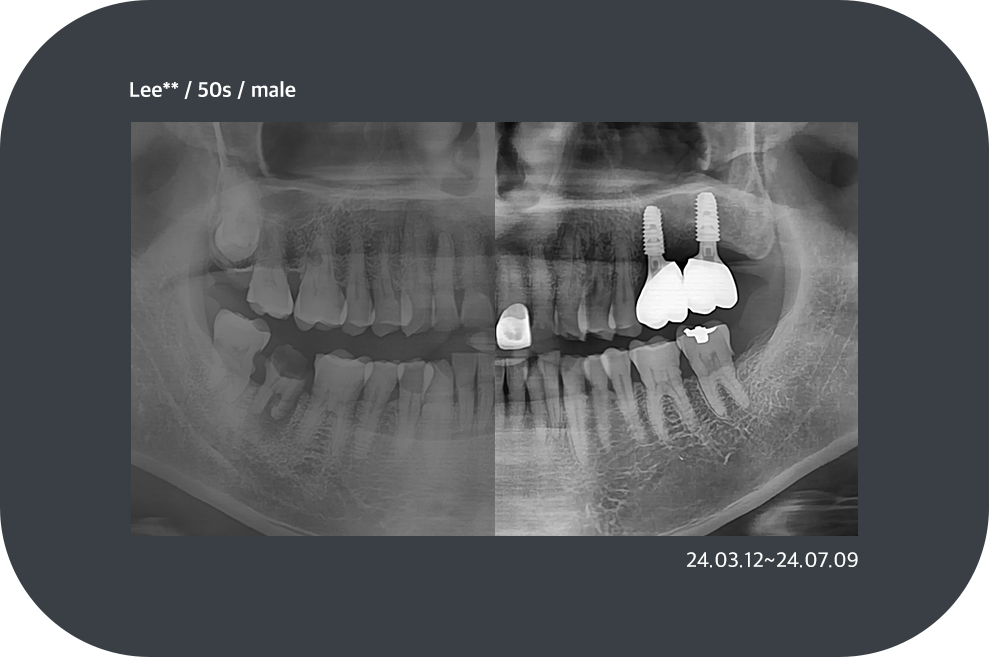

치료사례

임플란트 치료사례

implant_case01

implant_case02

implant_case03

implant_case04

*모든 증례 사진은 의료법 제23조, 제56조에 의거하여, 당사자의 동의하에 게시하였습니다.

*치료 사진은 모두 본원에서 치료한 환자분의 사진입니다.

*치료 사진은 모두 동일인의 사진이며, 동일조건에서 촬영하였습니다.

*개인의 차이에 따라 시술 및 수술 후 부작용이 발생할 수 있으며, 의료진과 충분한 상담을 받으시기 바랍니다.